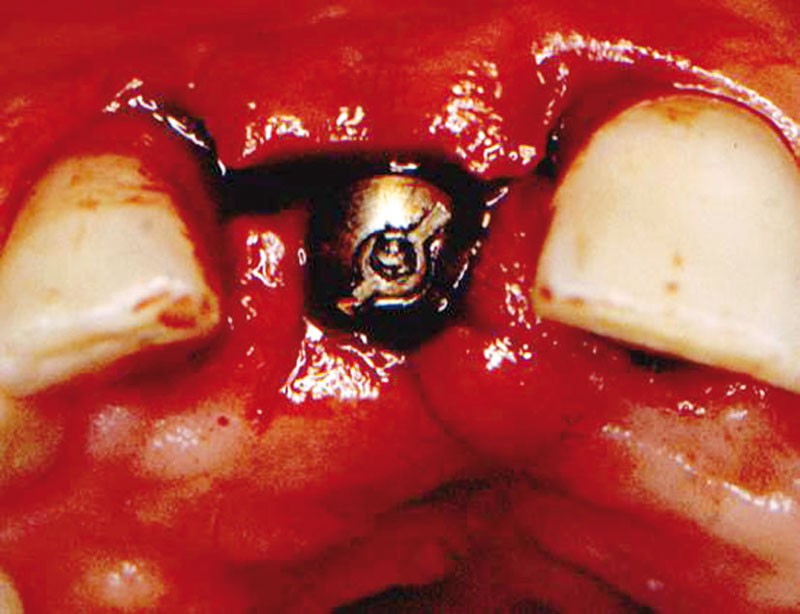

Technique chirurgicale. Après une anesthésie locale avec un vasoconstricteur (xylocaïne à 1100 000), une incision intra sulculaire partant des faces distales des deux dents adjacentes va être prolongée sur le sommet de la crête de façon à ce que la moitié vestibulaire de la vis de couverture se trouve dégagée quand le lambeau est soulevé.

Pour retirer la vis et en même temps créer des papilles, deux incisions palatines en S vont être tournées vestibulairement (fig. 3).